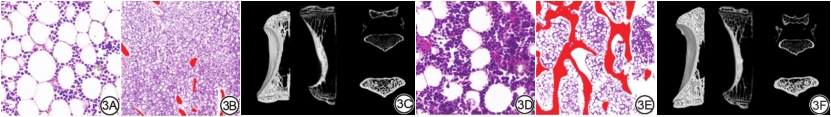

组织病理学苏木精-伊红染色显示,与对照组相比,第16周糖尿病兔腰椎骨髓脂肪细胞数量(32.875±11.051 vs. 71.667±13.125,P<0.01)增加,而骨小梁数量(11.375±1.506 vs. 4.333±1.211,P<0.01)与骨小梁面积(0.927±0.071 vs. 0.312±0.100,P<0.01)明显减少(图3)。

第16周IDEAL-IQ FF与组织病理学脂肪细胞计数呈正相关关系(r=0.539 95% CI:0.012~0.832;图4);IDEAL-IQ FF与Tb.Pf、SMI、Tb.Sp呈轻中度正相关关系,与BMD、TV、BV、BV/TV、TS、BS、BS/BV、BS/TV、Tb.N呈轻中度负相关关系(图5)。